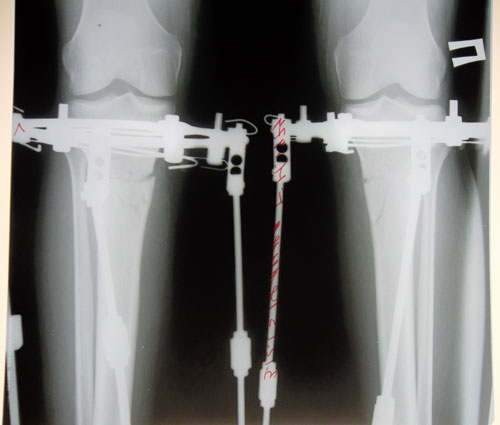

Основные крутки закончены!

57 ДНЕЙ С МОМЕНТА ОПЕРАЦИИ.